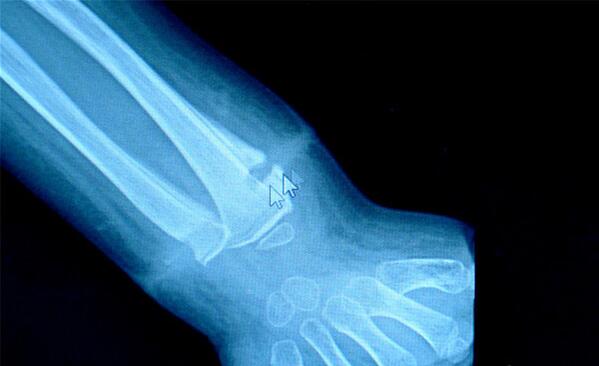

龙龙左手手腕的X光图。

“手术过程中发现孩子手腕上有一根橡皮筋,已经长进肉里了,深深地嵌入骨膜表面。”符松说,为龙龙做脓液引流时,他发现伤口深处有一条白色物体,一拉还有弹性。取出后他看到,让龙龙手腕流脓的“罪魁祸首”竟然是一根直径不到2cm的橡皮筋!